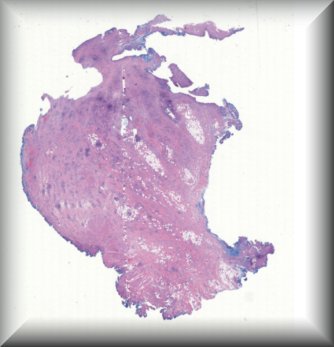

Thomas J. Cummings (Durham, North Carolina): 54-year-old male with multiple systemic infections underwent enucleation after 2 months of pain, redness and acute loss of vision. |